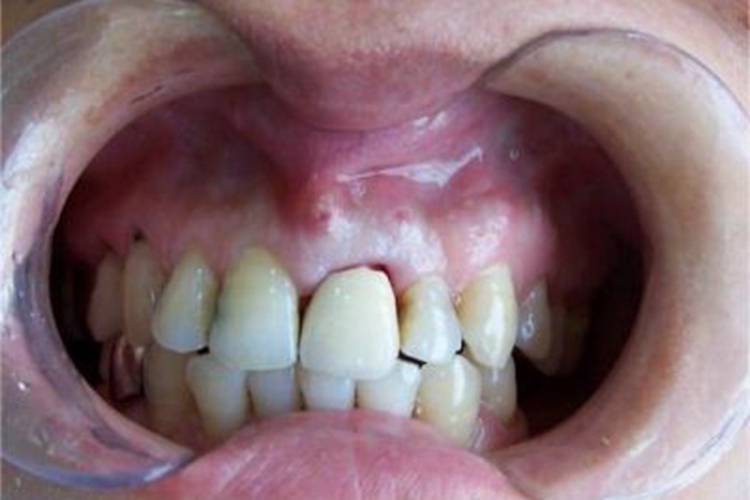

牙周脓肿急性期过后未及时治疗或反复急性发作,可导致慢性牙周脓肿,表现为牙龈表面有窦道开口,呈小孔状,针尖大小,按压时有少许脓液流出。